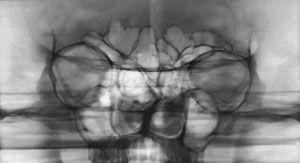

Лор-врачи после обзорных снимков очень любят назначать зонограммы (Рис. 1.) и томограммы (Рис. 2 а, б.) лицевого черепа. Это позволяет выделить интересующую область (например, пазухи) для детального осмотра. Есть даже гайморография – искусственное контрастирование гайморовых пазух. Востребована и у Лор-врачей и КТ. Ведь компьютерная томография чрезвычайно информативна.

Зонограмма средней зоны пациента с грубой деформацией лицевого черепа: гипертелоризмом, пороком формирования полости носа.